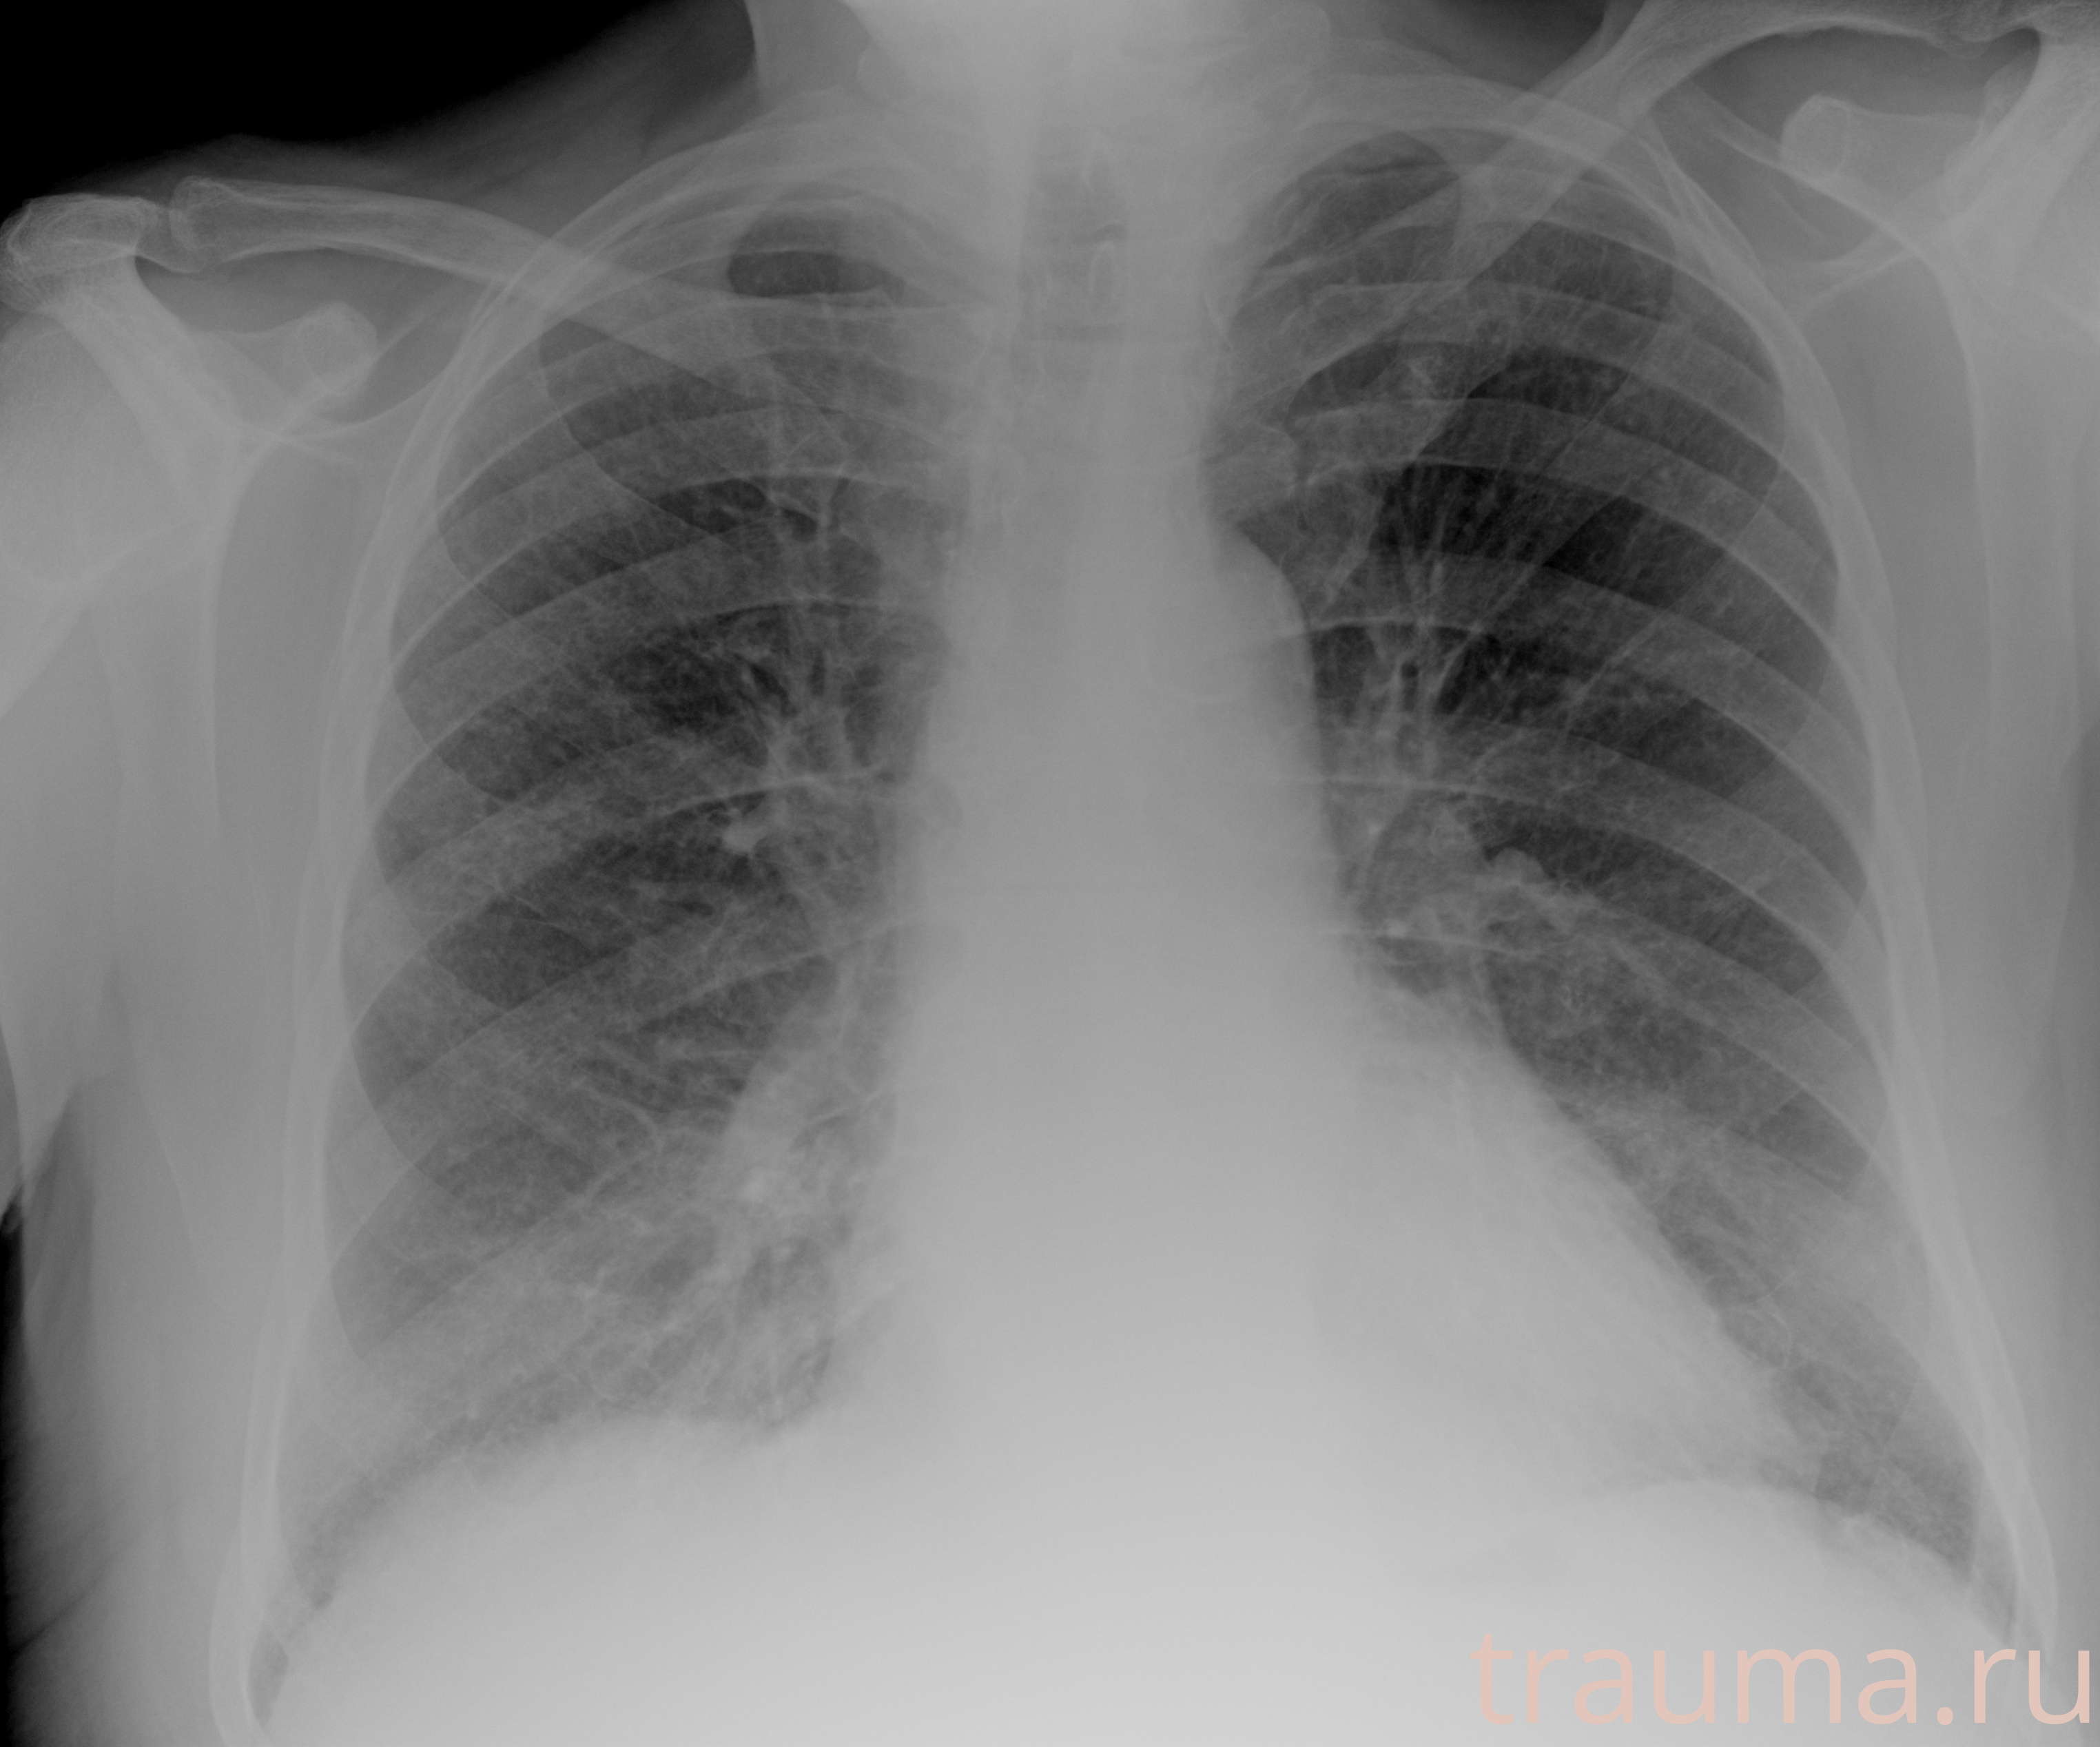

Рентгенограммы

Рентген на дому: по вашему адресу приезжает врач-рентгенолог, травматолог-ортопед с мобильным рентгеновским аппаратом, проводит диагностику травмы или заболевания, делает необходимые рентгенограммы, дает рекомендации по дальнейшему лечению. Получить качественные снимки в домашних условиях возможно благодаря уникальной методике, разработанной МосРентген Центром для института  Склифосовского

Яркость: 1   Контраст: 1   Инвертировать: 0 Увеличение: 1

Перетаскивайте мышь вверх/вниз для контраста, влево/право для яркости. Прокрутка колесом изменяет масштаб. Нажмите Сбросить для возврата к исходному изображению. При увеличении держите мышь в той области, которую хотите рассмотреть.